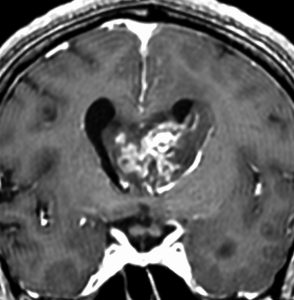

無症状で偶然発見された47歳女性の側脳室内上衣下腫

無症候で偶然発見された左側脳室前角尾状核頭に接したsubependymoma。定位脳生検で病理診断を得たましたが,3年間の観察で徐々に増大しました。左上が発見時,1年後(右上),2年後(左下),3年後(右下)

CTではやや低吸収,T1ガドリニウムでは低信号となりガドリニウム増強されません。小さな上衣下腫の場合は等吸収あるいは等信号のものも多いです。小さく点状に造影されている部分があるがこれは定位脳手術痕(track)です。

左中前頭回からの経皮室法 left middle frontal gyrus transcortical approach で全摘出できました(右図)。